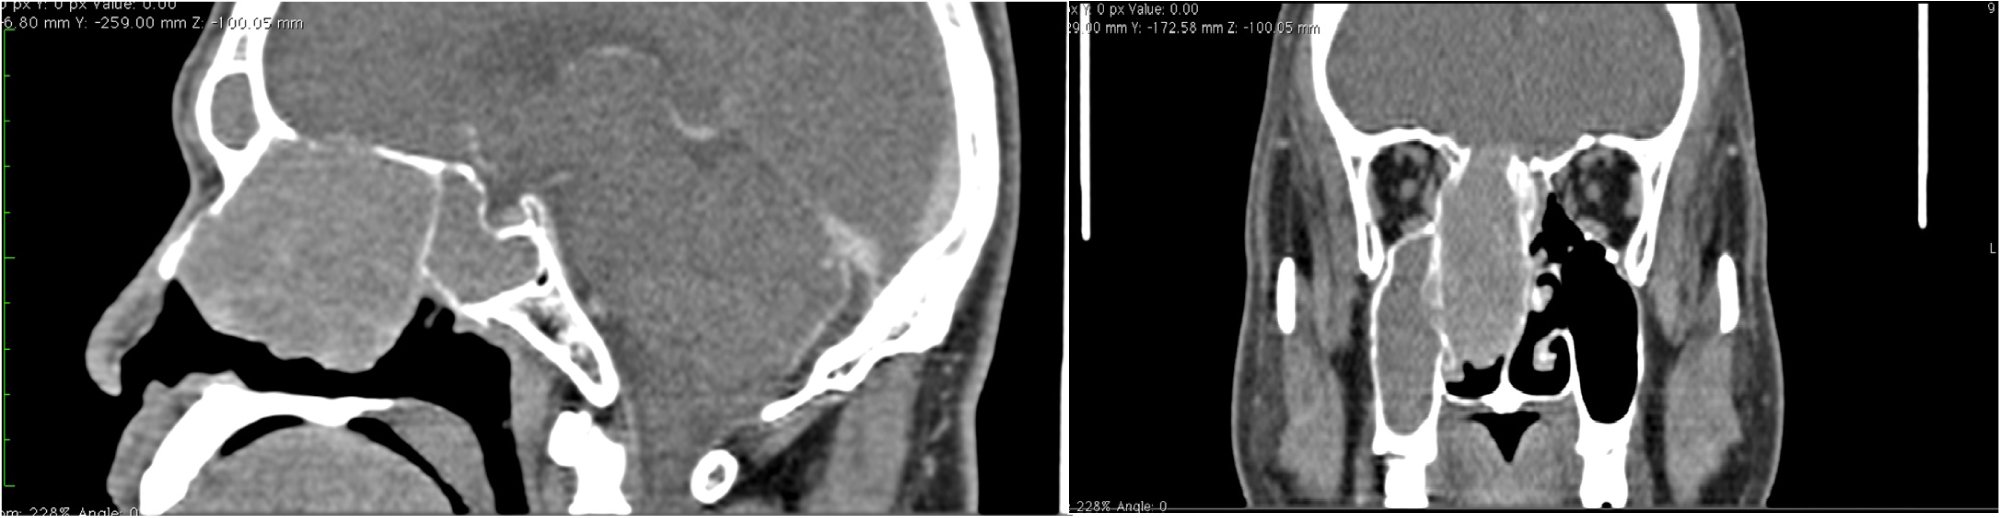

A 53-year-old Filipino male presented with two-year history of right nasal obstruction with rhinorrhea and epistaxis. He was initially managed medically as a case of nasal polyposis. He denied any history of visual impairment, seizure, headache, and weakness. Despite good compliance with the medications prescribed to him, no relief of symptoms was noted. He went to another specialist for a second opinion. Paranasal sinus CT Scan (Figure 1) was done which revealed a large expansile mass in the right nasal cavity. This was followed by MRI of the paranasal sinuses (Figure 2) with gadolinium that revealed a right heterogeneously enhancing nasal mass with no intracranial extension. Punch biopsy of the mass revealed features suggestive of hemangiopericytoma, ectopic meningioma, and glomangiopericytoma. Immunohistochemical staining was suggested for a definitive diagnosis. Immunostain with Vimentin and Epithelial Membrane Antigen were strongly positive. This confirmed the diagnosis of ectopic meningioma. The patient was advised surgery, but was lost to follow up.

Figure 1: Sagittal and coronal CT scans with contrast showing a mass filling the right nasal cavity enhanced by the contrast associated with filling of ipsilateral maxillary sinus. View Figure 1